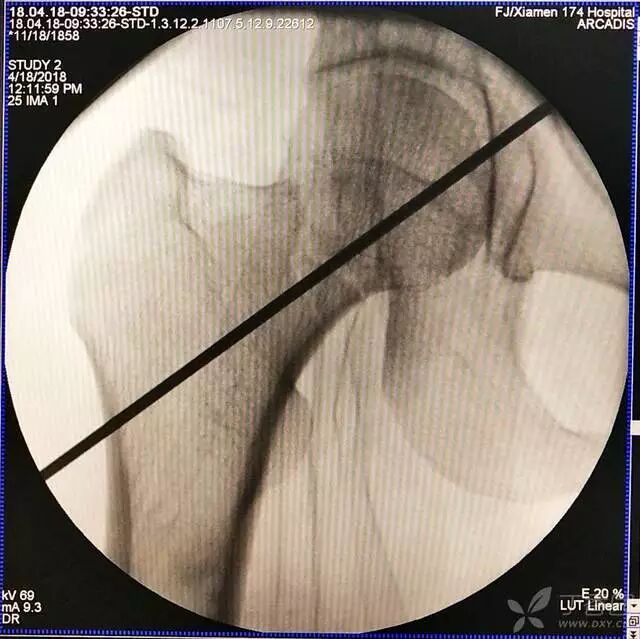

3. 再努力一把就基本成了

牵引床怎么用视频详解:如何不使用牵引床做好一台股骨颈骨折?_https://www.jmylbn.com_新闻资讯_第11张

4. 先体外放置一枚导针导引进针方向